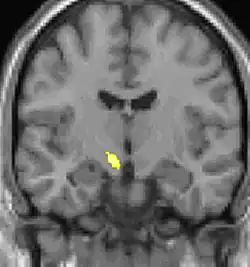

| La tomographie par émission de positons (TEP) montre les zones du cerveau étant activées durant la douleur | ||

| La morphométrie voxel par voxel (VBM) montre les différences structurelles des zones du cerveau | ||

Les images par tomographie à émission de positron indiquent les régions du cerveau qui sont activées lors de la douleur, par rapport aux périodes sans douleur. Elles montrent les régions du cerveau qui sont toujours actives durant la douleur en jaune/orange (appelé "matrice-douleur"). La zone au centre (dans les trois vues) est spécifiquement activée uniquement pendant la crise. Les photos sur la ligne du bas (effectuées par VBM) montrent les différences structurelles entre les patients souffrant d'AVF et des personnes saines : seulement une partie de l'hypothalamus est différente[50],[51].